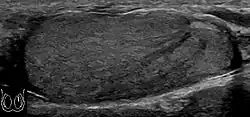

Patients with testicular lymphoma are usually old aged around 60 years of age, present with painless testicular enlargement and less commonly with other systemic symptoms such as weight loss, anorexia, fever and weakness. Bilateral testicle involvements are common and occur in 8.5% to 18% of cases. At sonography, most lymphomas are homogeneous and diffusely replace the testis [Fig. 7]. However focal hypoechoic lesions can occur, hemorrhage and necrosis are rare. At times, the sonographic appearance of lymphoma is indistinguishable from that of the germ cell tumors [Fig. 8], then the patient's age at presentation, symptoms, and medical history, as well as multiplicity and bilaterality of the lesions, are all important factors in making the appropriate diagnosis.

Primary leukemia of the testis is rare. However, due to the presence of blood-testis barrier, chemotherapeutic agents are unable to reach the testis, hence in boys with acute lymphoblastic leukemia, testicular involvement is reported in 5% to 10% of patients, with the majority found during clinical remission. The sonographic appearance of leukemia of the testis can be quite varied, as the tumors may be unilateral or bilateral, diffuse or focal, hypoechoic or hyperechoic. These findings are usually indistinguishable from that of the lymphoma [Fig. 9].